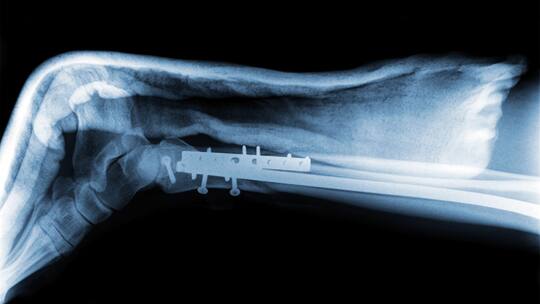

Frage: Mein Sohn brach sich als Schüler beim Snowboarden das Bein. Nun ist er Lehrling und beim Arbeitgeber versichert. Wer zahlt die Entfernung der Platte und der Schrauben?

Die Versicherung des Arbeitgebers ist dann zuständig, wenn sich ein Unfall während der Versicherungszeit ereignet hat. Da sich Ihr Sohn aber in der Schulzeit das Bein brach, muss nicht die Unfallversicherung des Lehrbetriebs für die Kosten der zweiten Operation aufkommen, sondern die Krankenversicherung.